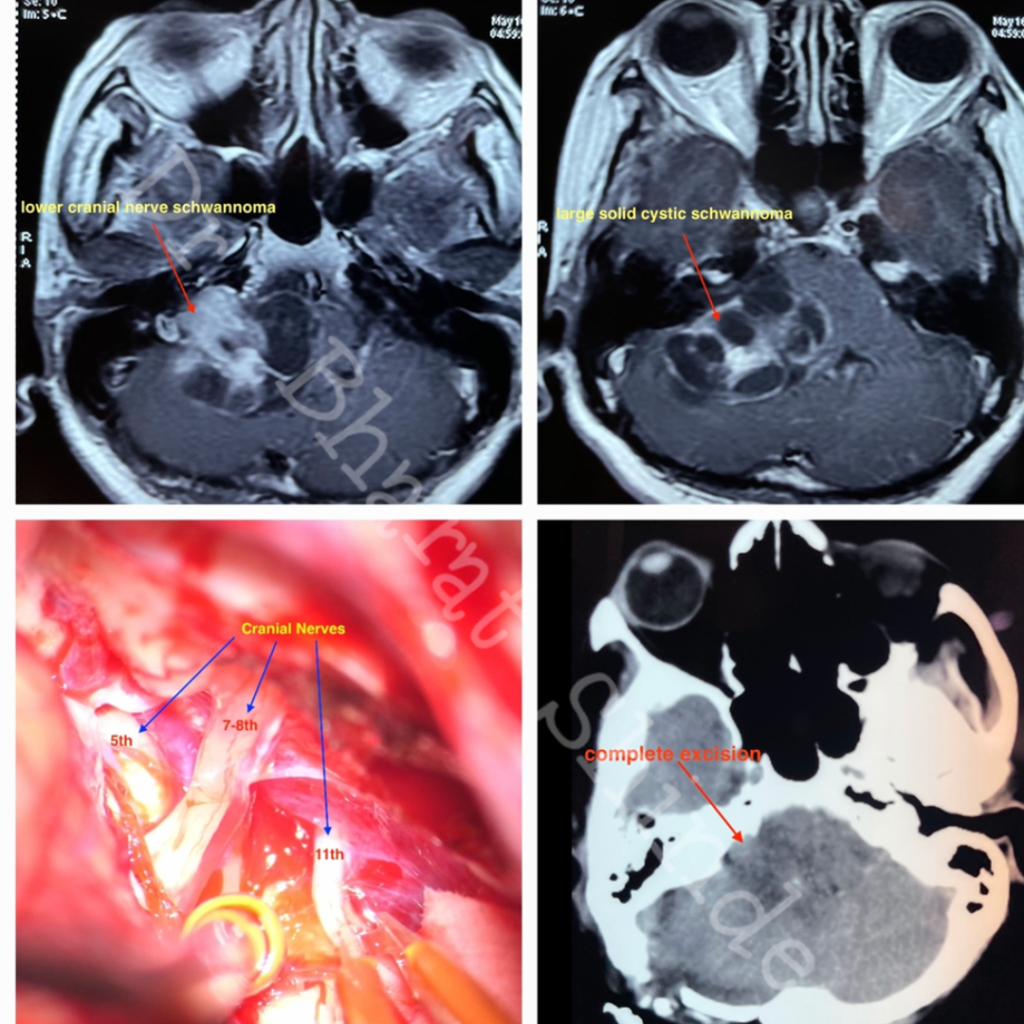

Which nerves are called as Lower cranial nerves:

What is Schwannoma ?

Nerves are covered with Schwann cells. Tumor arising from it is called as Schwannoma.

What are the clinical features of Schwannoma ?

Schwannoma arising from any nerve impair function of that nerve. As lower cranial nerves helps in swallowing movements ,patients having lower cranial nerve schwannoma present with swallowing difficulty , nasal regurgitation, cough while drinking water.As tumor size increases it compresses brainstem, cerebellum leading patient to have swaying while walking , difficulty in balancing .

Are these tumors treatable ?

Smaller tumors less than 3 cm can be treated with GKRS , a form of radiotherapy. It controls growth rate of tumor. It requires close follow up and regular interval MRI of patient to see Increase in size.

Larger tumor requires surgery where part of bone behind ear is removed and tumor is decompressed with microscope.

Lower Cranial nerves entering jugular fossa

Facial -Vestibulocochlear nerve complex entering IAM

Spinal Accessory Nerve